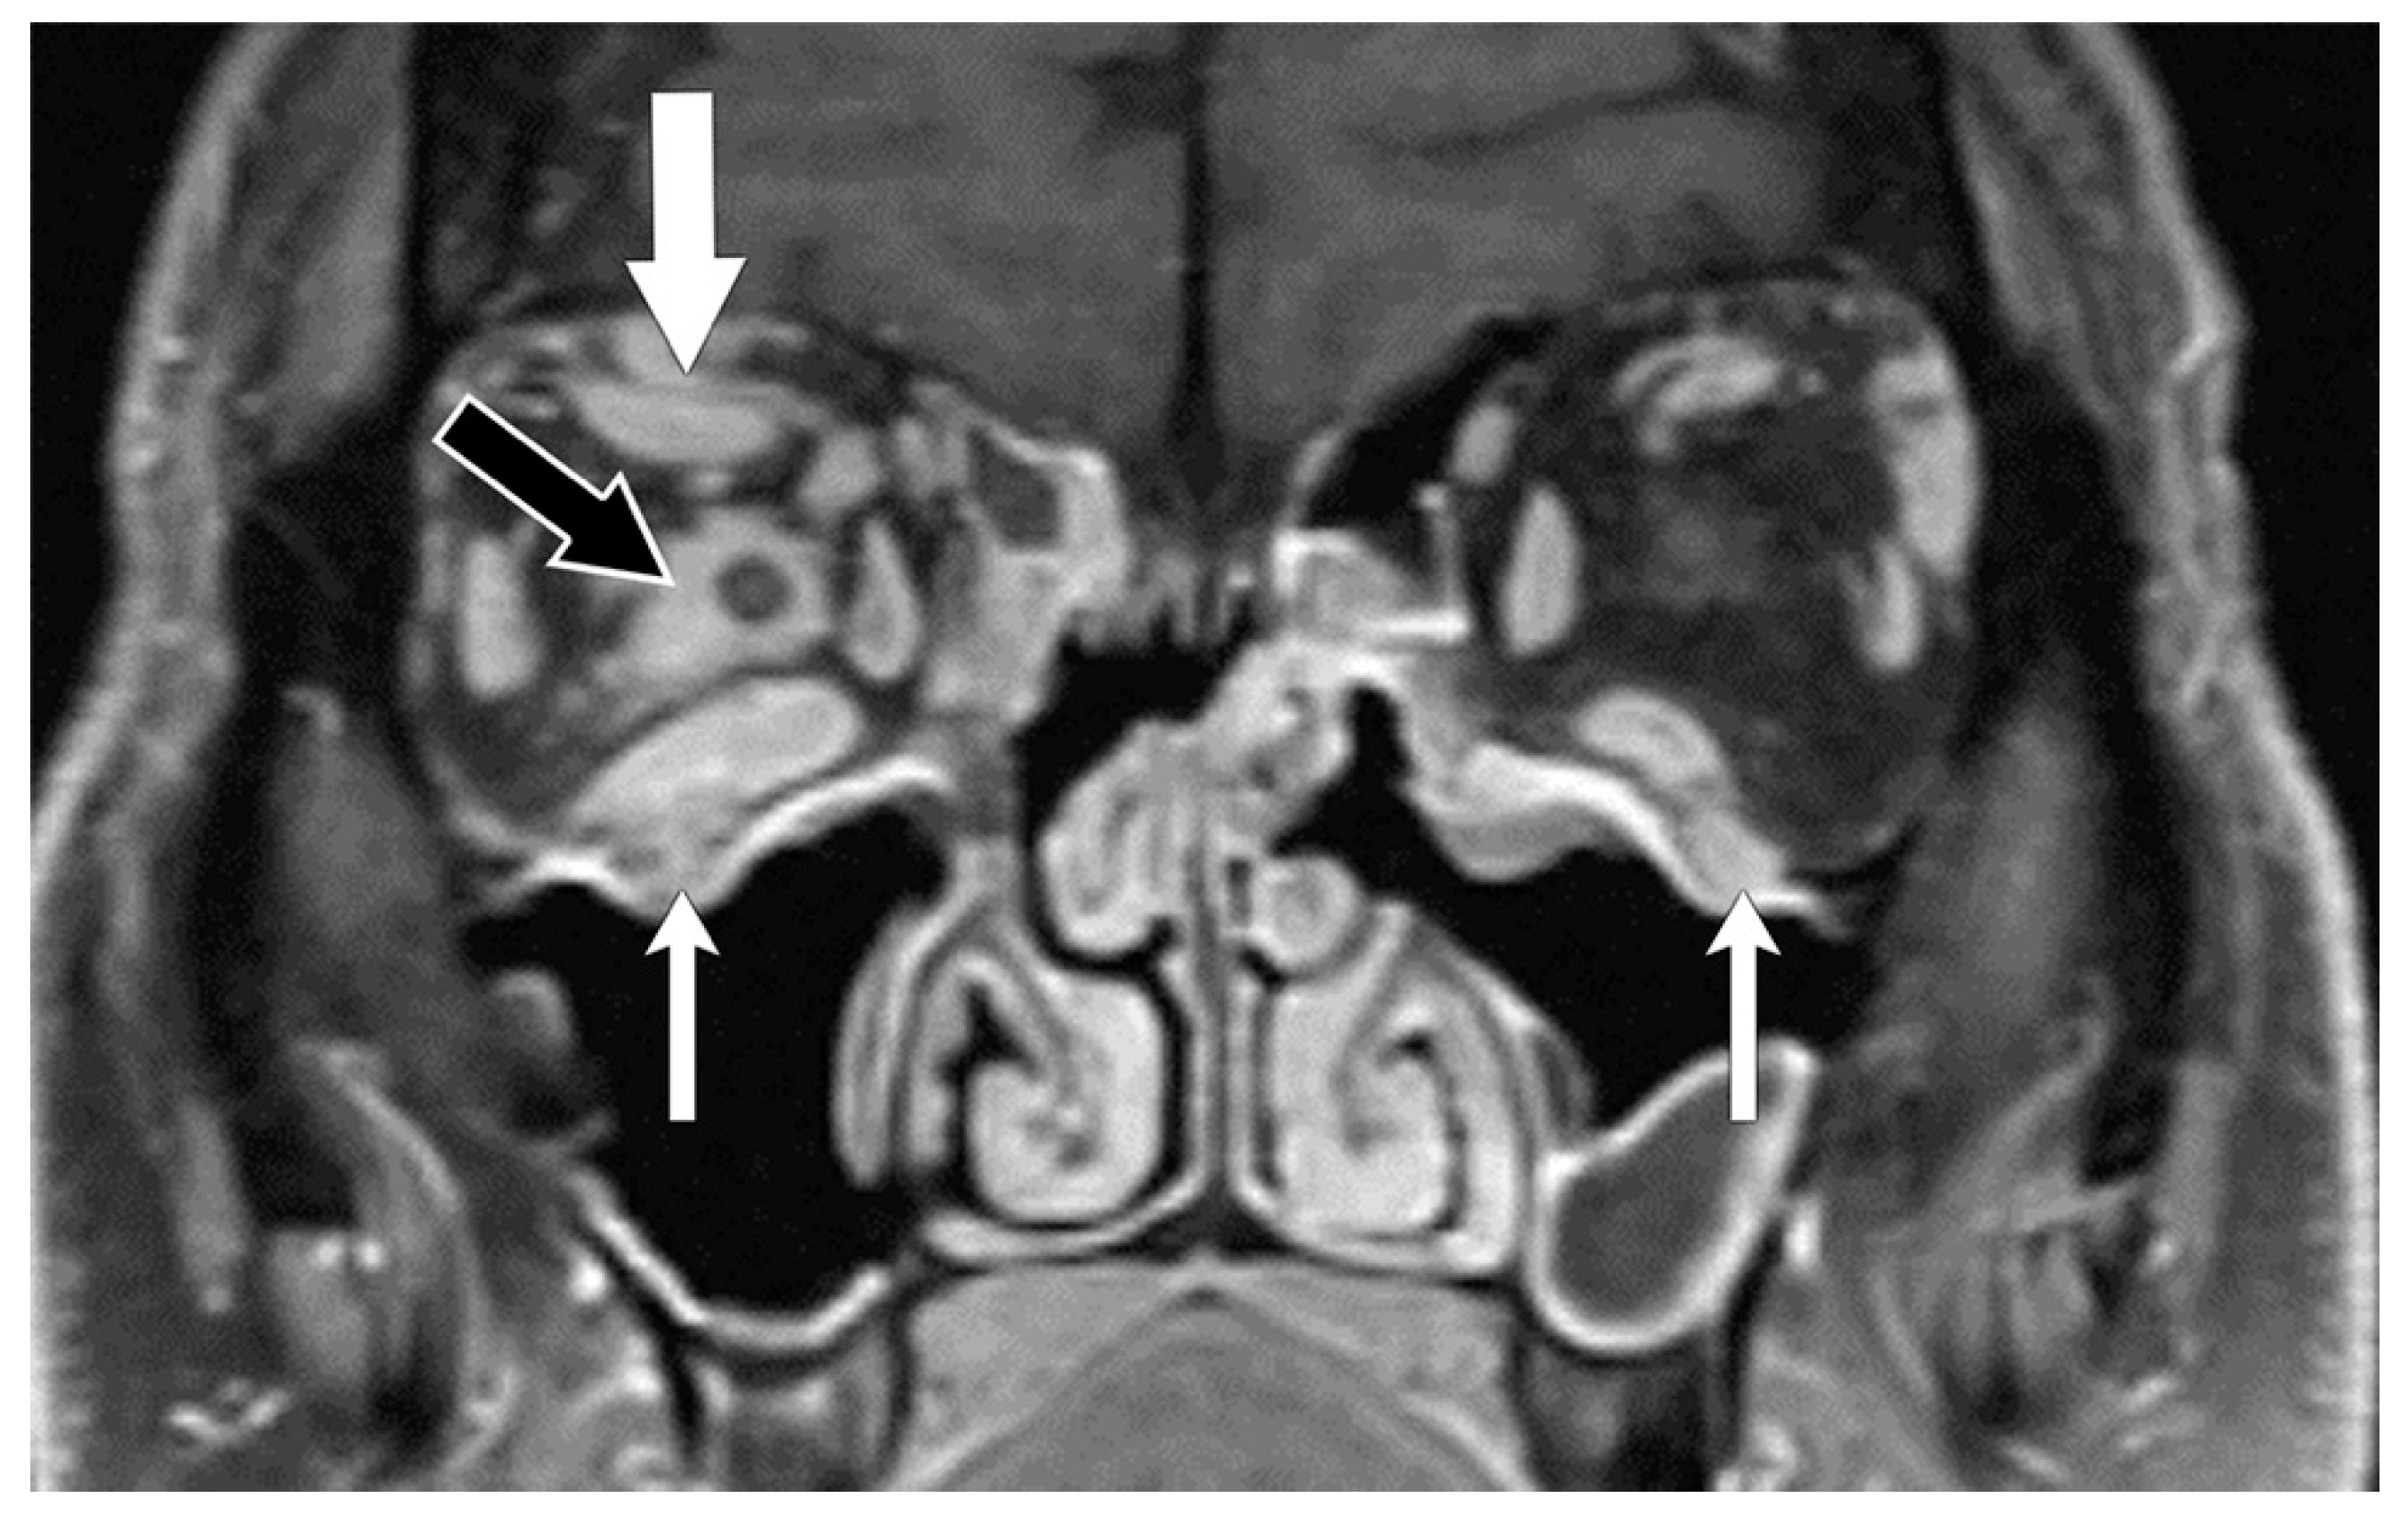

5. Radiological Diagnosis

5.2. Magnetic Resonance Imaging (MRI)

5.4. Diagnosis of Compressive Optic Neuropathy (CON)

6. Radiological Differential Diagnosis